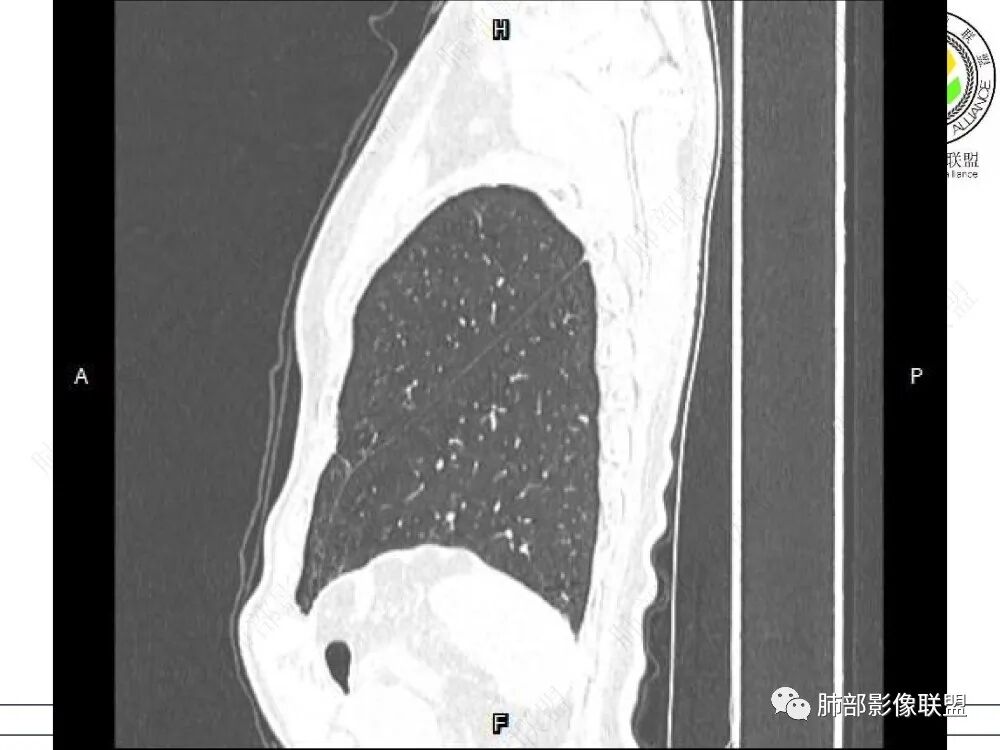

2、影像特点:左肺上叶尖后段病灶结合病史考虑消融术后改变,双肺下叶胸膜下可见多发大小不等的实性结节,周围似乎有晕,边缘平直为主,未见深分叶,部分可见邻近胸膜牵拉,张力不高,增强后呈轻中度强化。

5、分布:病灶分布多位于胸膜下,可紧贴胸膜,也可与胸膜邻近,病灶长轴与胸膜平行。(划重点,分布特点非常重要)